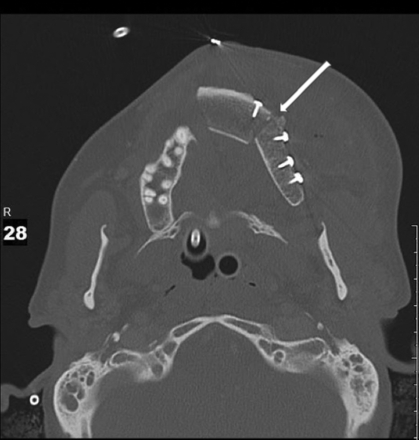

Axial imaging of a normal ICFF demonstrating a thick sheet of bone with a hyperattenuated cortex and intermediate attenuation of the trabecular surface. An osteotomy site is demonstrated and filled with corticocancellous bone (arrow). Images were obtained in the immediate postoperative period. Left cheek prominence is an expected immediate postoperative finding in the flap setting. Normal cheek cosmesis will be obtained over time.

Contouring of the iliac bone can be accomplished by performing a unicortical osteotomy in the lateral surface and the iliac crest, which permits the bone to be “green stick fractured,” if a bend in the bone is required to accommodate to the normal architecture of the palatomaxillary complex. By creating this cut in this orientation, the DCIA and DCIV are preserved along the medial surface. The resulting “open osteotomy” is usually filled with corticocancellous bone chips that are harvested from the remaining iliac bone. Over time, this osteotomy will form solid bone. It should be noted that the goal of reconstruction is to place the neoalveolar maxillary ridge in direct apposition to the mandibular alveolus to facilitate dental restoration and normal occlusal relationships.